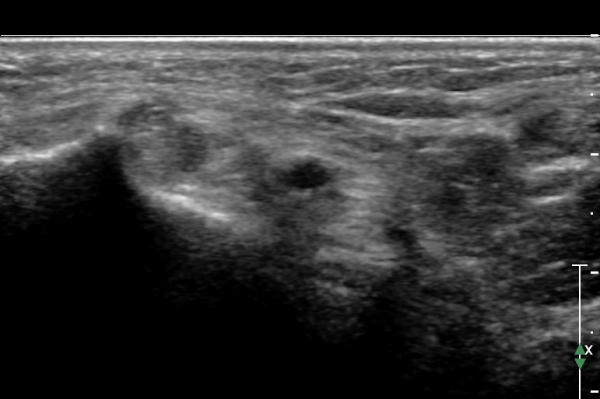

ÃÊÀ½ÆÄ ¼Ò°ß :  ¹ß¸ñ ³»Ãø Á¾´Ü¸é °Ë»ç¿¡¼­ Á¤»ó ÀûÀÎ ¼Ò°ßÀ» º¸ÀÓ(»çÁø 1).